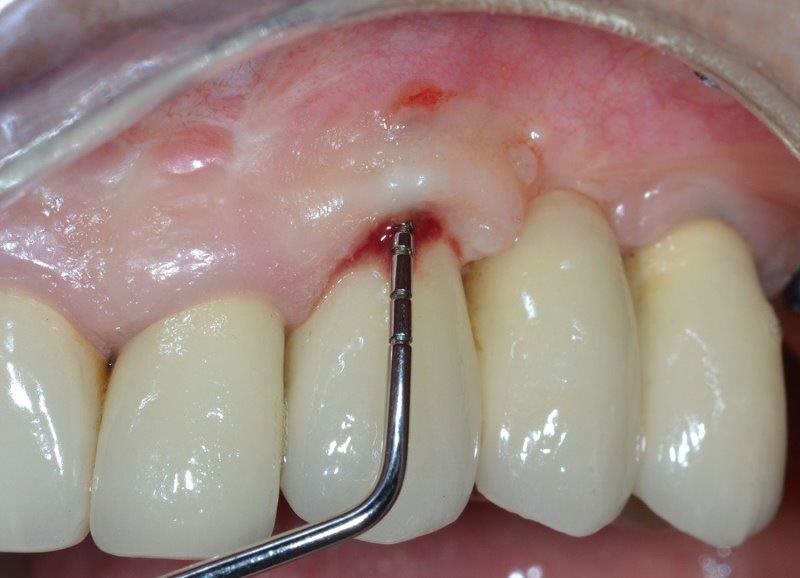

Because of its limited ability to prove a detailed view of the three-dimensional anatomical structures, periapical X-ray examination may not provide full information about important parameters such as alveolar bone thickness, anatomy, size, extension and location of bone defects. To overcome this limitation, clinicians must cross-correlate the data from X-ray examination and peri-implant probing (Fig. 6). Clinical parameters such as mBI, mPlI, PD and implant mobility (IM) were registered at baseline.

HBT and VBD around the implant were measured with a periodontal probe, along with periapical X-ray examination and intraoperative evaluation of the new regenerated tissue density using a periodontal probe at a pressure of approximatively 0.25 N to confirm a satisfactory quality and quantity of this tissue (Fig. 18). Healing abutments were then placed over the implants (Fig. 19).